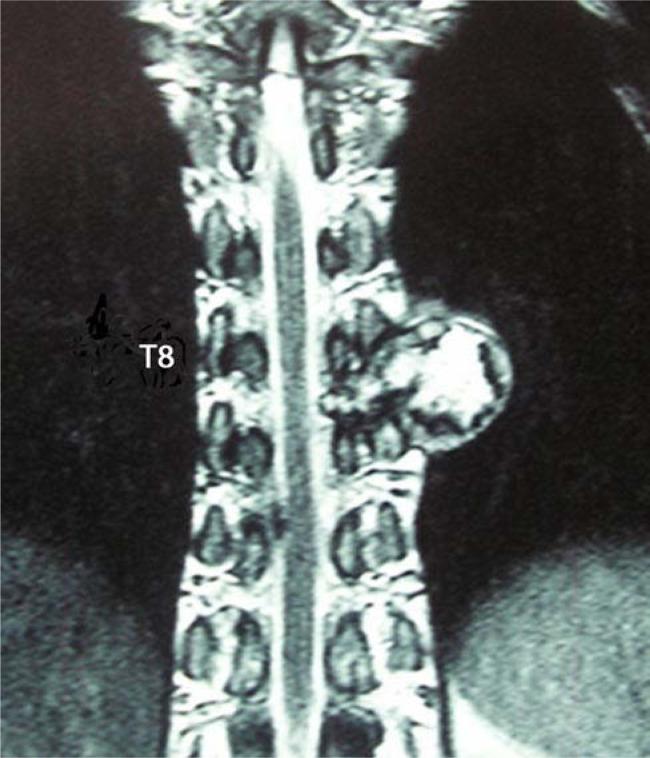

The incidence of osteochondroma is rare and only 2% of such tumors are found in the spine area. When they are found in the vertebral column, less than 1% of all osteochondromas and few tumors occur in the thoracic vertebrae. An osteochondroma arising from the transverse process of the vertebra is even rarer, especially following from the thoracic transverse process. Here we report a giant solitary osteochondroma arising from the thoracic transverse process of T8 vertebra and involving the corresponding transverse process and rib. A 28-year-old man presented with a progressive thoracic node, and neuroradiological evaluation of the spine showed a giant mass lesion involving the transverse process of T8 vertebra and concomitant corresponding facet joint and rib on the left side. At surgery, a firm and cartilaginous tumor originating from the transverse process was radically excised and surgical curettage of the lesion was performed. It is concluded that accurate and prompt diagnosis requires a high index of suspicion followed by surgical treatment to prevent severe morbidity in cases of primary spinal column tumors. The histological examination of this patient revealed the lesion was osteochondroma. The best choice of treatment for spinal osteochondromas is surgical excision or curettage and spinal stabilization, if necessary.